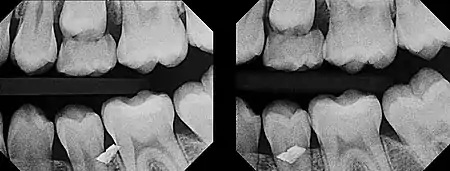

In 1909, Charles A. Clark described a radiographic procedure for localizing impacted teeth to determining their relative antero-posterior position.[1] If the two teeth (or, by extension, any two objects, such as a tooth and a foreign object) are located in front of one another relative to the x-ray beam, they will appear superimposed on one another on a dental radiograph, but it will be impossible to know which one is in front of the other. To determine which is in front and which is behind, Clark proposed his SLOB rule, as a complicated set of three radiographs, but which can be simplified as follows using just two:

- Expose another film while angle of the x-ray beam has been changed. If an object moves in the same direction as the source of the x-ray beam, it is lingual to the other object. If the object moves in the opposite direction of the source, it is buccal to the other object.

In 1952, Richards amended this rule using only 2 radiographs,[2][3] asserting that the object positioned more buccally will move more relative to the object positioned more palatally or lingually.

As a generalization, but not specifically stated as part of Richards' buccal object rule, the more buccal an object is (i.e. the closer it is to the x-ray source) the more it will move in the second radiograph when repositioning the x-ray source.